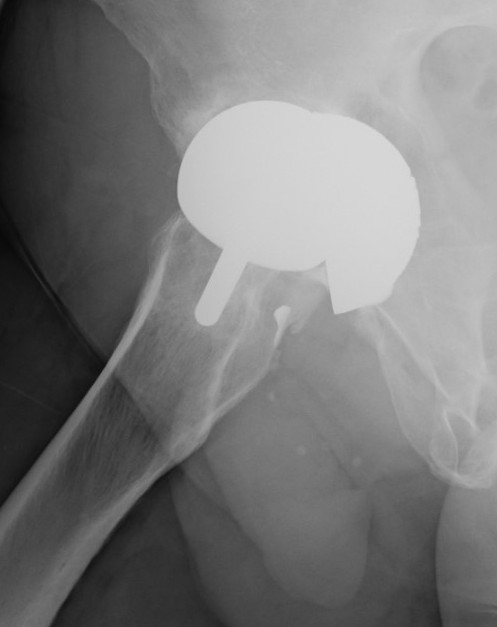

Birmingham hip resurfacing

Concept

Femur - removal of femoral head cartilage and resurfacing with metal

Acetabulum - standard technique

Bearing surface - metal on metal

Birmingham Resurfacing

Oversized head

Varus Femoral Component

Femoral head notching

Open Acetabular Component - may cause point loading and increased metal wear